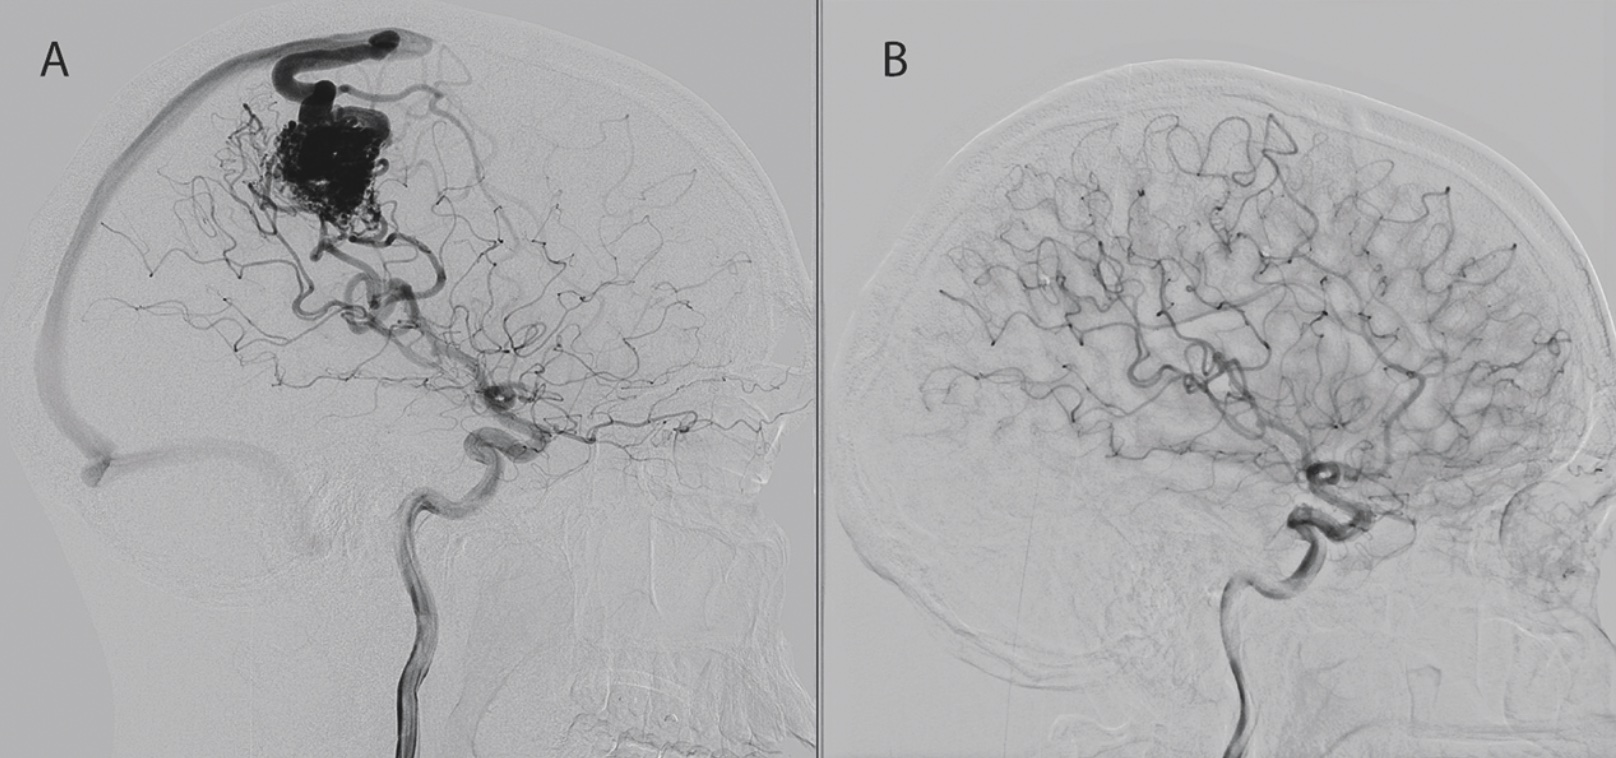

Trigeminusneuralgi, eller »tic douloureux« som tillståndet ibland träffande benämns, definieras som attackvis (2‒120 sekunder) påkommen smärta, strikt begränsad till någon eller flera av trigeminusnervens 3 sensoriska grenar. Trigeminusneuralgi tenderar att förlöpa skovvis. Vid svåra skov har patienten ofta upprepade smärtattacker vid minsta stimulus, vilket gör att patienterna inte förmår äta, tala eller sköta sin munhygien. Tillvaron blir ofta högst inskränkt, med rädsla för att allt ovan kan utlösa smärtan. Initial behandling vid skov ska alltid vara farmakologisk, oftast med karbamazepin eller oxkarbazepin som förstahandsval. Detta kommer dock inte att ha tillräcklig effekt på en del patienter, som kommer att uppleva besvärande biverkningar, och dessa kan vara aktuella för ett neuro­kirurgiskt ingrepp. Mikrovaskulär dekompression är något förenklat det enda ingrepp som anses kunna bota trigeminusneuralgi [10]. Mikrovaskulär dekompression förutsätter att MRT av hjärnan påvisat ipsilateral s k neurovaskulär konflikt vid hjärnstamsutträdet för trigeminusnerven (ca 50 procent) och innebär ett öppet mikrokirurgiskt ingrepp genom s k retrosigmoidal kraniotomi [10]. De övriga ingreppen ger sällan bot, men kan vara mycket värdefulla för patienter där mikrovaskulär dekompression inte är möjlig eller medför stora risker. Transoval ballongkompression är ett snabbt perkutant ingrepp, som kan användas som en semiakut behandling vid svåra skov (Figur 3). Ca 85‒90 procent blir momentant smärtfria och kan börja trappa ut sitt läkemedel direkt [11]. Recidiv av smärtan sker oftast inom dryga året, även om variationen är stor vad gäller svårighetsgraden på nästkommande skov. Ett alternativ till ballongkompression är termolesion, som är vanligare i bland annat Centraleuropa. Stereotaktisk strålkirurgi (i Sverige används gammaknivsbehandling) för trigeminusneuralgi är inte invasiv, och risken för allvarliga biverkningar är väldigt låg. En nackdel är dock att endast ca 70 procent av behandlade patienter får effekt och att denna normalt dröjer 1‒3 månader [12].

Figur 3. Intraoperativ fluoroskopi under en transoval ballongkompression för trigeminus­neuralgi.